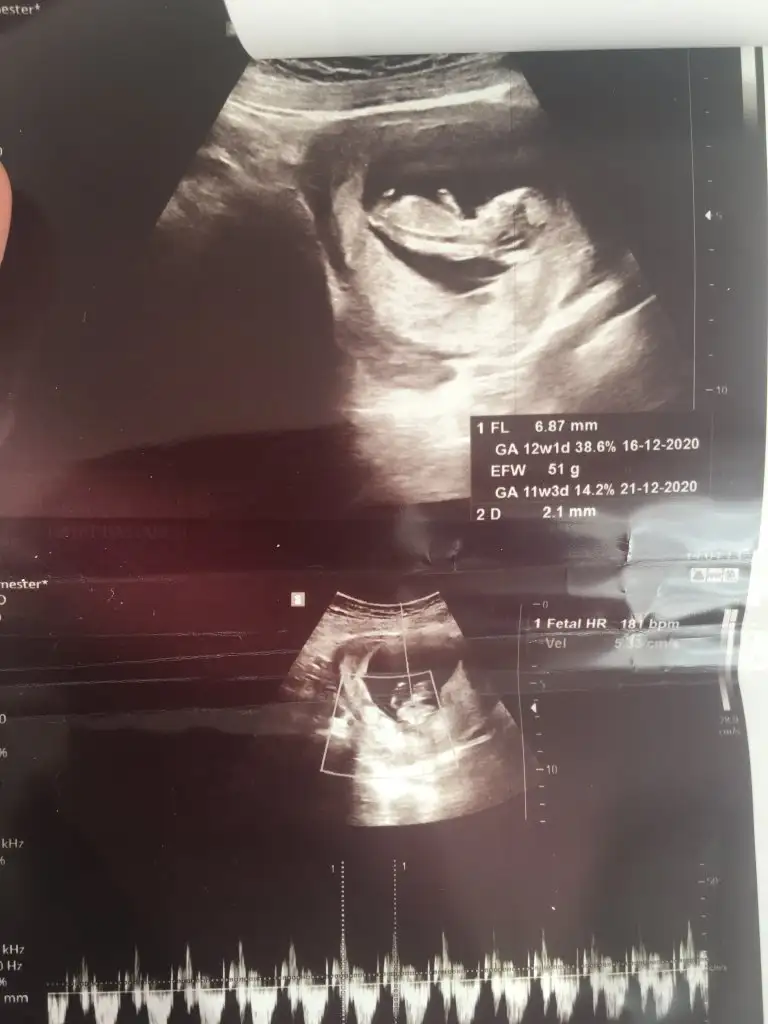

bu da diger acidan fotografi ayagi kapatmis gibi amabu bu haftaki goruntusu 12. hafta gecen hafta erkek demistiniz ama emin olamamistiniz@ikrameyra

Hem net değil hemde 11 12 13 hafta olmalıBana da tahmin yapabilir misiniz 15+1 göstermedi cinsiyeti bugün bıcırık :)Ikra meyra

Mrb 13 haftalik olduk cok sukurKız gibi net de değil kız sanki 12-13 olunca tekrar usg paylaşın

Kız gibiMrb 13 haftalik olduk cok sukur